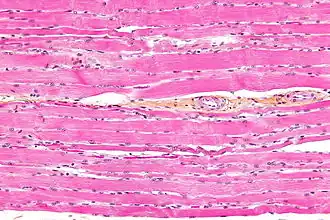

Micrograph of HPS stained skeletal striated muscle (fibularis longus).

Striated muscle tissue is a muscle tissue that features repeating functional units called sarcomeres. Under the microscope, sarcomeres are visible along muscle fibers, giving a striated appearance to the tissue. The two types of striated muscle are skeletal muscle and cardiac muscle.